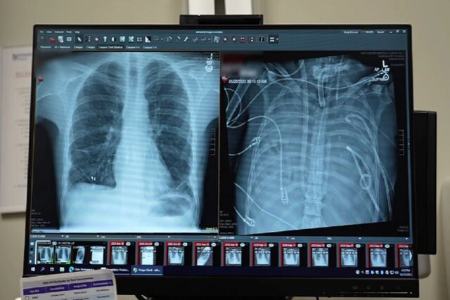

یک مرد ۳۳ ساله بعد از اینکه گروه پزشکی، اعضای بدنش را با یک سیستم ریه مصنوعی خارجی جایگزین کردند که توسعه یافته بود تا او را زنده نگه دارند که بتواند پیوند دو ریه دریافت کند، به مدت ۴۸ ساعت بدون ریههایش زنده ماند.

قبل از قرار گرفتن روی سیستم ریه مصنوعی، این مرد دچار سندرم حاد دیسترس تنفسی شده بود که یک وضعیت اغلب تهدیدکننده حیات است که در آن ریهها نمیتوانند اکسیژن کافی جذب کنند و این مشکل توسط ویروس آنفلوانزا ایجاد شده بود. سپس او روی ونتیلاتور قرار گرفت، اما دچار عفونت مقاوم به دارو شد. این عفونت باعث شد قسمتهایی از ریههای او پر از چرک شود و او وارد شوک سپتیک شود که در این مرحله قلب و کلیههایش شروع به از کار افتادن کردند.

بهارات میگوید: او خیلی بیمار بود، دچار ایست قلبی شد و در حال مرگ بود. از آنجا که این مرد خیلی بیمار بود که پیوند ریه دریافت کند، گروه پزشکان تصمیم گرفتند ریههای او را که منبع عفونت بود، بردارند.

به طور شگفتانگیز، مرد شروع به بهبود سریع کرد. در عرض ۴۸ ساعت، او همه داروها برای حمایت از فشار خون را کنار گذاشت، عملکرد کلیه او کاملا بازیابی شد و قلب او به طور طبیعی کار میکرد. در این مرحله، مرد پیوند دو ریه را دریافت کرد و سالها بعد هیچ نشانهای از رد عضو یا اختلال عملکرد ریه نشان نداد. اکنون تقریبا سه سال از انجام این کار گذشته است و حال بیمار واقعا خوب است.